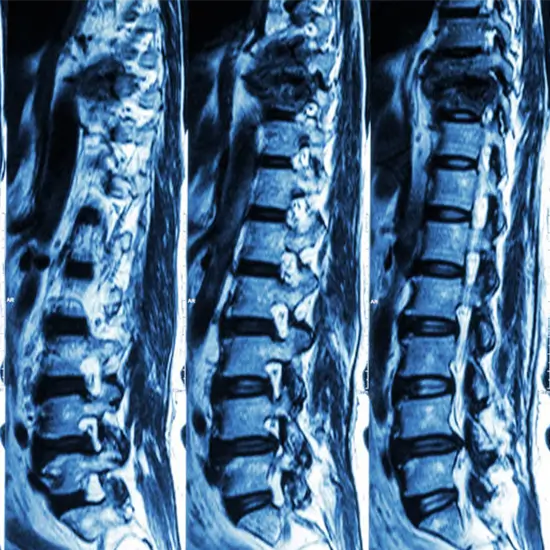

MRI of the lumbar spine can scan the lower back and surrounding soft tissues. The lumbar spine, or lower back, has five vertebrae. L1-L5 are these vertebrae. This scan uses a contrast dye to better see inside tissues and arteries.

The doctor will prescribe this test to detect severe back pain, birth defects (congenital) that damage the spine and evaluate the extent of injury to the lower spine and frequent lower back pain.